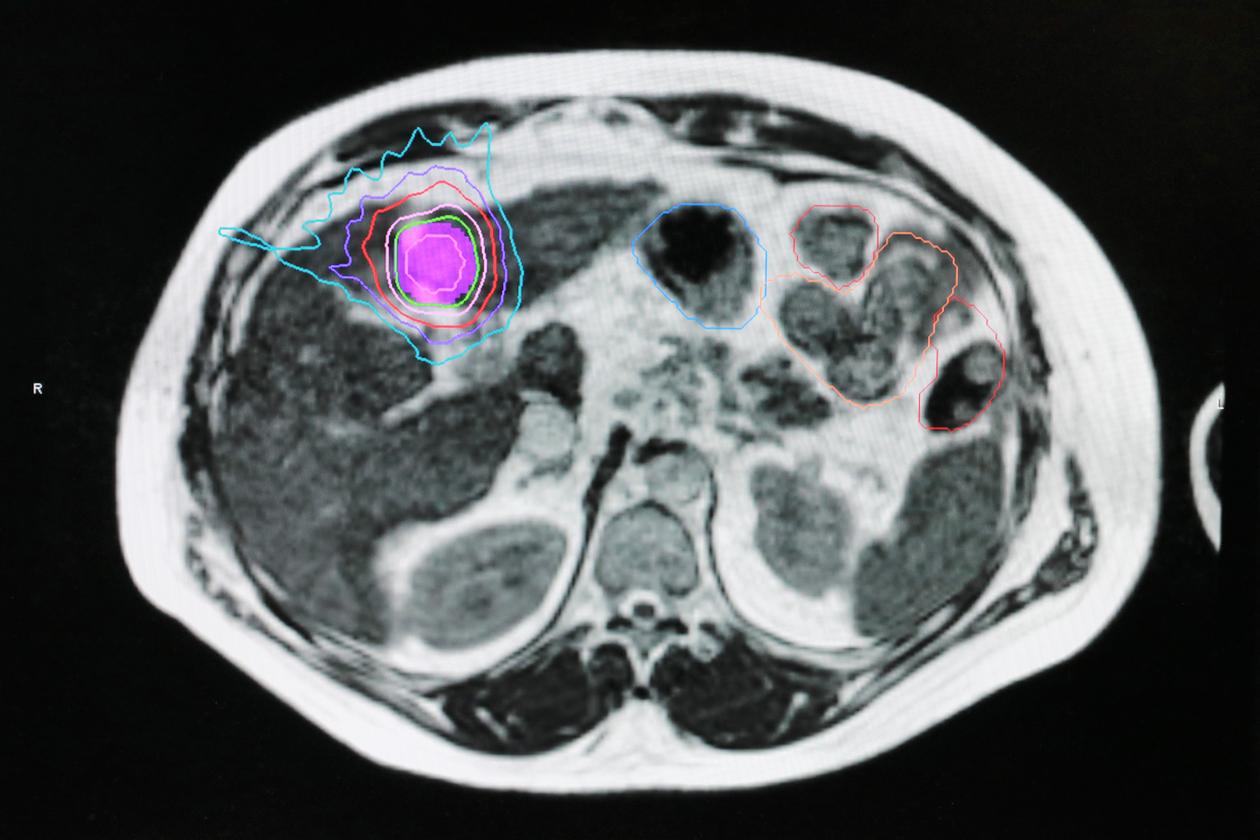

L’Institut régional du cancer de Montpellier (ICM) propose, lui, depuis fin 2020, un logiciel d’IA qui recalcule, dans le cas d’une radiothérapie guidée par scanner, le protocole à suivre en fonction de l’évolution de la tumeur. Cet algorithme « permet, en cours de traitement, de réduire la zone irradiée et de protéger les tissus sains si la tumeur a diminué », relève le professeur David Azria, directeur scientifique de l’ICM. « Tout est encore perfectible, et je ne crois pas au logiciel providentiel mais, dans ce cas précis, l’IA n’est pas seulement une aide au diagnostic, c’est aussi une aide à la thérapeutique », note l’oncologue, également président de la Société française de radiothérapie oncologique (SFRO).

L’ICM et l’hôpital d’Herlev, au Danemark – tous deux pionniers mondiaux dans l’utilisation de ce dispositif –, travaillent main dans la main pour aller plus vite dans l’étude clinique, encore en cours. Montpellier s’est focalisé sur les cancers gynécologiques et de la vessie, Herlev sur ceux de la prostate.

Autre innovation utilisant de l’IA dans l’Hérault, mais sur une autre machine, « une radiothérapie guidée par l’IRM permet de cibler des tumeurs du foie ou du pancréas, organes dont on établit les contours et que l’on suit ainsi mieux ». Le service de radiothérapie des hôpitaux parisiens de la Pitié-Salpêtrière et Tenon sont venus se former sur ces applications à Montpellier.